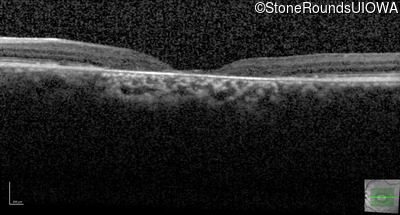

AR Stargardt Disease (IIA)

Age at visit: 30 years

Age at visit: 31 years

Age at visit: 32 years

Age at visit: 33 years